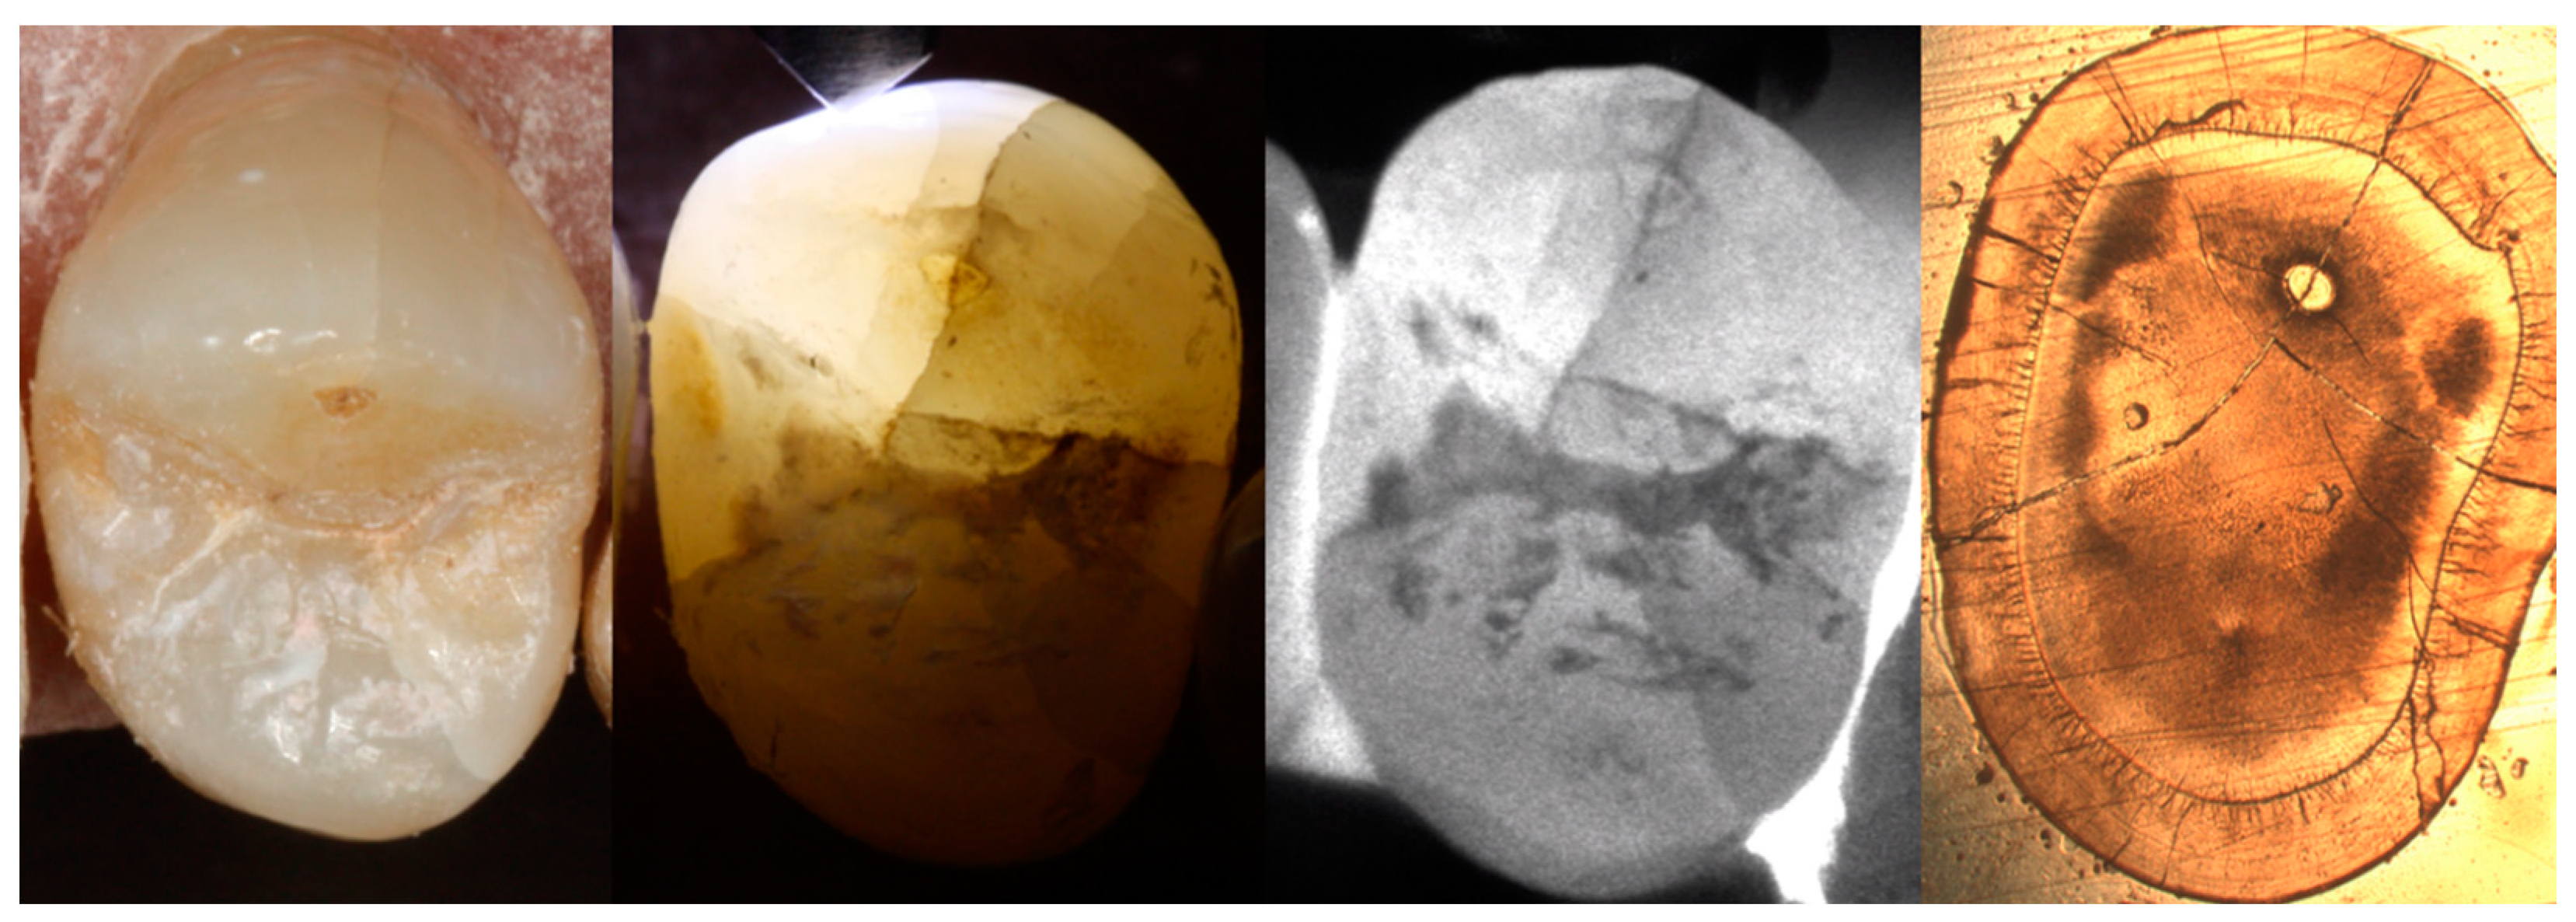

2.2. Documentation of Enamel Cracks

2.3. Visualization of Enamel Cracks